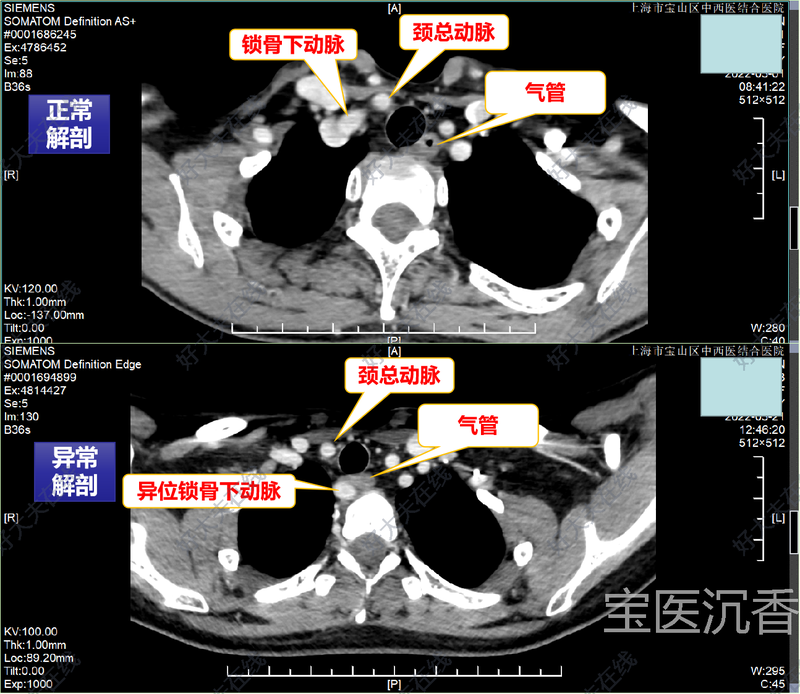

治療前 術(shù)前通過增強(qiáng)CT檢查,發(fā)現(xiàn)右側(cè)鎖骨下動(dòng)脈變異,精準(zhǔn)預(yù)測(cè)極罕見的喉不返神經(jīng),為手術(shù)安全提供了有力保障 治療中 術(shù)中常規(guī)行甲狀腺癌根治術(shù),尋找及辨認(rèn)喉不返神經(jīng)入喉處及起始部,全程顯露神經(jīng),為手術(shù)安全提供極大的保障 治療后 治療后3天 術(shù)后發(fā)聲良好,飲水無嗆咳等不適,順利出院。 喉返神經(jīng)及喉不返神經(jīng)都是支配聲帶的神經(jīng)。這條神經(jīng)很細(xì),直徑幾乎只有1毫米,通過影像等手段是無法發(fā)現(xiàn)的。如果術(shù)中稍微不注意,這條位置異常的神經(jīng)就會(huì)被傷及,而后果輕則失去發(fā)音功能,重者則造成呼吸困難、窒息、甚至死亡。 喉不返神經(jīng)是喉返神經(jīng)一種罕見的解剖變異,發(fā)生概率大約0.5%~1.0%,而且多見于右側(cè),左側(cè)者及其罕見。喉不返神經(jīng)的存在增加了外科手術(shù)風(fēng)險(xiǎn)及神經(jīng)損傷概率,而操作上的慣性思維是導(dǎo)致術(shù)中誤傷喉不返神經(jīng)的重要原因之一。 如何能夠正確的預(yù)見喉不返神經(jīng)呢?關(guān)鍵是如何提前預(yù)知呢?尋找右側(cè)鎖骨下動(dòng)脈起始異常!正常情況下右鎖骨下動(dòng)脈與頸總動(dòng)脈是頭臂干的延續(xù)。右側(cè)鎖骨下動(dòng)脈起始異常即有右側(cè)喉不返神經(jīng)存在。 外科正在不斷向微創(chuàng)和精細(xì)化方向發(fā)展,追求在解決疾病的同時(shí)不傷害或盡量少傷害正常組織。 我們團(tuán)隊(duì)?wèi){借高超的專業(yè)技能和敏銳的專業(yè)嗅覺,術(shù)前觀察到血管存在的異常解剖,精準(zhǔn)預(yù)測(cè)喉不返神經(jīng)存在的可能,術(shù)中發(fā)現(xiàn)了喉不返神經(jīng)這一深埋的“陷阱”,在完整切除甲狀腺腫瘤病灶的同時(shí)做到了對(duì)神經(jīng)的安全保護(hù),彰顯了我們團(tuán)隊(duì)面對(duì)甲狀腺疑難、復(fù)雜手術(shù)的綜合處理能力。